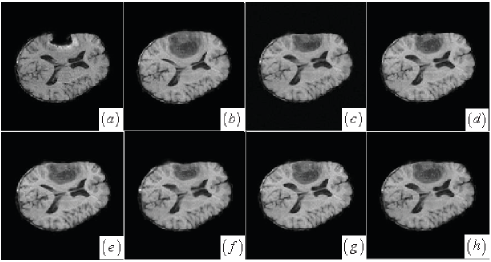

Another grayscale image registration is matching pre- and post-operative brain tumor images. Brain tissue severely suppressed by tumor in the preoperative image (Fig. 11(b)) expands after tumor resection. Tumor resection not only brings missing correspondences into the tumor region of the post-operative image (Fig. 11(a)) but also incurs local large deformations that are caused by brain shift. A successful registered result of this case should properly deform pre-operative brain tissue according to the post-operative image regardless of tumor resection. Visual inspection has revealed that the proposed, AMI, AMM and LOF methods (see Fig. 11(c)-(d),(g)) apparently perform better than the DDD and BMI methods (see Fig. 11(e)-(f)) because the local brain deformation resulted from the latter two methods is either insufficient or somewhat excessive. This visual valuation is further confirmed by validating landmark-based registration error in the following section.

The MRE and SD of the manually selected landmarks for the six methods in the three grayscale image registration are listed in Tab. 1. The proposed method for the Mickey image achieves the smallest registration error of pixels while the registration errors of AMI, DDD, BMI, AMM and LOF methods are greater than or equal to pixels. Compared with other method, the proposed method and AMI have achieved sub-pixel registration accuracy for the brain tumor resection images with the registration errors of and pixels, respectively. As for the flower image, the proposed method gets the smallest registration error of pixels, while the registration errors of other five methods are greater than or equal to pixels. In average, the proposed method maintains almost the best performance in comparison with other five methods. Although the orignial AMI method in the brain tumor resection image registration has a slight advantage over the proposed method, using cost-function masking makes AMM method worse than the proposed method in matching locally deformed structures. Simply setting the brain-tumor-region’s value to zero by cost-function masking is not enough to accurately match local salient structures with missing correspondences and local large deformations. Due to the LOF method only considering the effect of large displacments, its performance is not desired for the nonrigid registration with both missing correpondences and local large deformations.